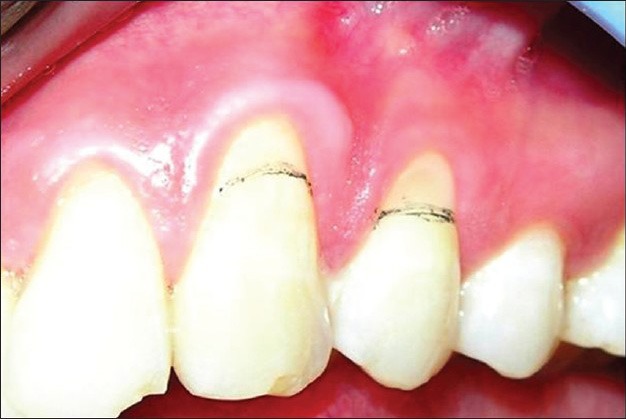

Când vorbim despre retractii gingivale ne referim la o patologie frecvent întâlnită în practica stomatologică, cu o prevalență bine documentată în creștere odată cu vârsta și cu apariție constantă în contexte clinice specifice, indiferent de grupa de vârstă. Retractia gingivala este asociată cel mai frecvent cu periajul traumatic, cu un fenotip parodontal subțire sau cu factori iatrogeni și este definită ca deplasarea marginii gingivale apical față de joncțiunea smalț-cement (cemento-enamel junction – CEJ), cu expunerea cementului radicular și a dentinei subiacente. Din punct de vedere clinic, această modificare se corelează cu sensibilitate dentinară, risc crescut de carii radiculare, abraziuni cervicale și dificultăți în menținerea unei igiene orale eficiente.

Complexitatea situației crește semnificativ atunci când recesiunile sunt multiple și adiacente. În aceste cazuri, afectarea continuă a marginii gingivale nu mai poate fi abordată ca un defect localizat, deoarece implică întregul segment muco-gingival. Consecințele se reflectă atât la nivel estetic, prin modificarea armoniei gingivale, cât și la nivel biologic, prin impactul asupra vascularizației și stabilității țesuturilor moi. Manipularea chirurgicală devine mai delicată, iar conservarea integrității papilelor interdentare și a aportului sanguin local devine un obiectiv central, în special în zonele frontale ale arcadei.

Sursă foto: PMC4296465